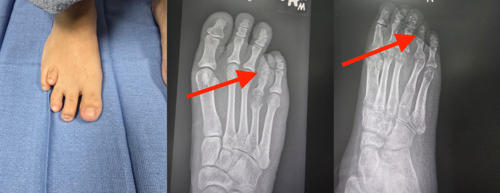

Johns Hopkins Aramco Healthcare (JHAH) has become the first hospital in the Eastern Province to offer routine corrective surgery for brachymetatarsia, a foot deformity that causes a patient’s toe to appear significantly shorter than the others.

Dr. Samer Bondokji, a consultant podiatric surgeon at JHAH, who is recognized for his expertise in limb-lengthening surgery and complex foot reconstruction, performed the hospital’s first toe-lengthening procedure on a brachymetatarsia patient in August last year. JHAH is now offering metatarsal lengthening surgery as a routine service to all patients who suffer from the deformity.

Patients with brachymetatarsia have one or more metatarsals — bones in the middle of the foot — that are significantly shorter than the others. This makes one or more of their toes look unusually short. Brachymetatarsia is most common in the fourth metatarsal, which affects the toe next to the little toe.

To bring a patient’s toe into line with the others, a surgeon cuts the shortened metatarsal bone and attaches a device known as an external fixator. The patient is discharged the same day. While at home, the patient makes small adjustments to the fixator every few days to slowly lengthen the metatarsal bone.

After about 12 weeks, when the metatarsal has reached the desired length and the new bone has strengthened sufficiently, the patient visits the outpatient clinic to have the fixator removed. They can then walk out of the clinic wearing protective shoes, and within a few days, they are able to wear the footwear of their choice.